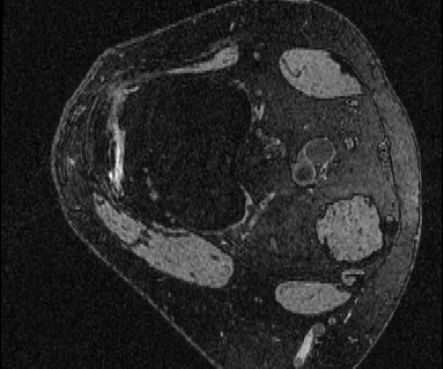

OAI Knee MRI We train and test on the split published with [22], with 2532 training examples and 301 test pairs from the Osteoarthritis Initiative (OAI) [16]444https://nda.nih.gov/oai. We evaluate using the mean Dice score of tibial and fibial cartilage. To compare directly to [22, 7, 23] we train and evaluate at [80x192x192].

| Moving Image | Warped Image | Fixed Image | Moving Image | Warped Image | Fixed Image |